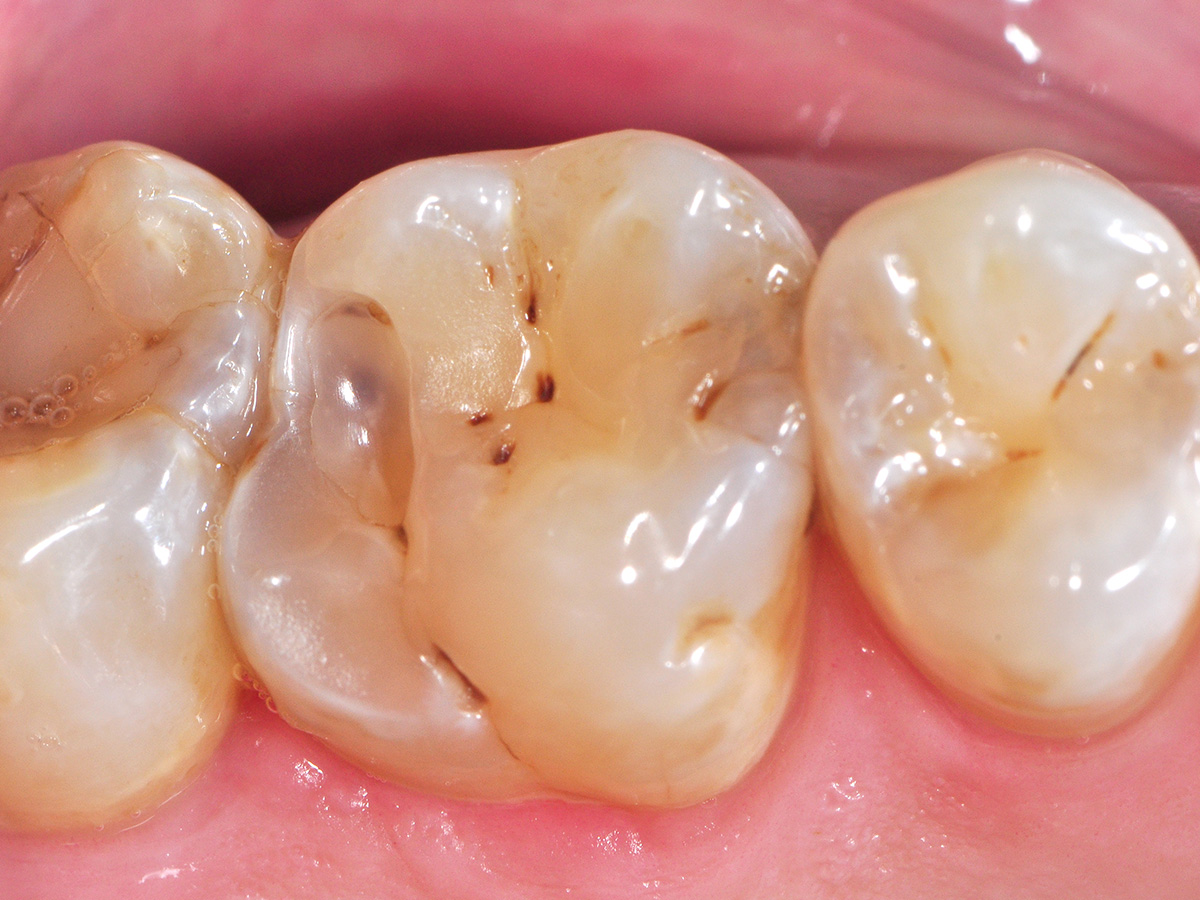

Abbildung 2

Nach Kofferdam-Applikation wurden die kariösen Defekte sauber exkaviert und mit einer Ringmatrize sowie zusätzlichem myQuickmat Forte Spannring (beides Polydentia) für die weitere Versorgung vorbereitet. Um eine optimale Separation für möglichst stramme Kontaktpunkte zu erreichen ist es sinnvoll, immer nur einen Spannring zu setzen, weil sich sonst die Kräfte gegenseitig annullieren würden.